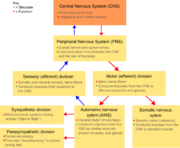

| 29. 5. 2010, 19:40 | NS diagram.png (soubor) |  | 101 kB | Webmaster | 1 | |